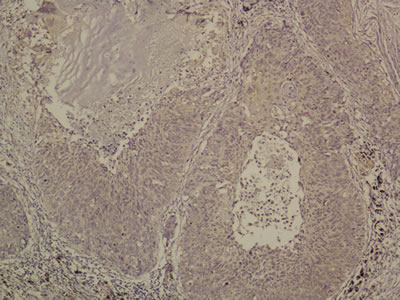

OLR1 expressed on tumor cells. Among all these 131 specimens of squamous NCSLC, OLR1 expressed in either one or both of the cell membrane and cytoplasm, in a focal or scattered pattern (Figure 2).

Figure 2: Immunohistochemistry for OLR1. Original magnification 200x.